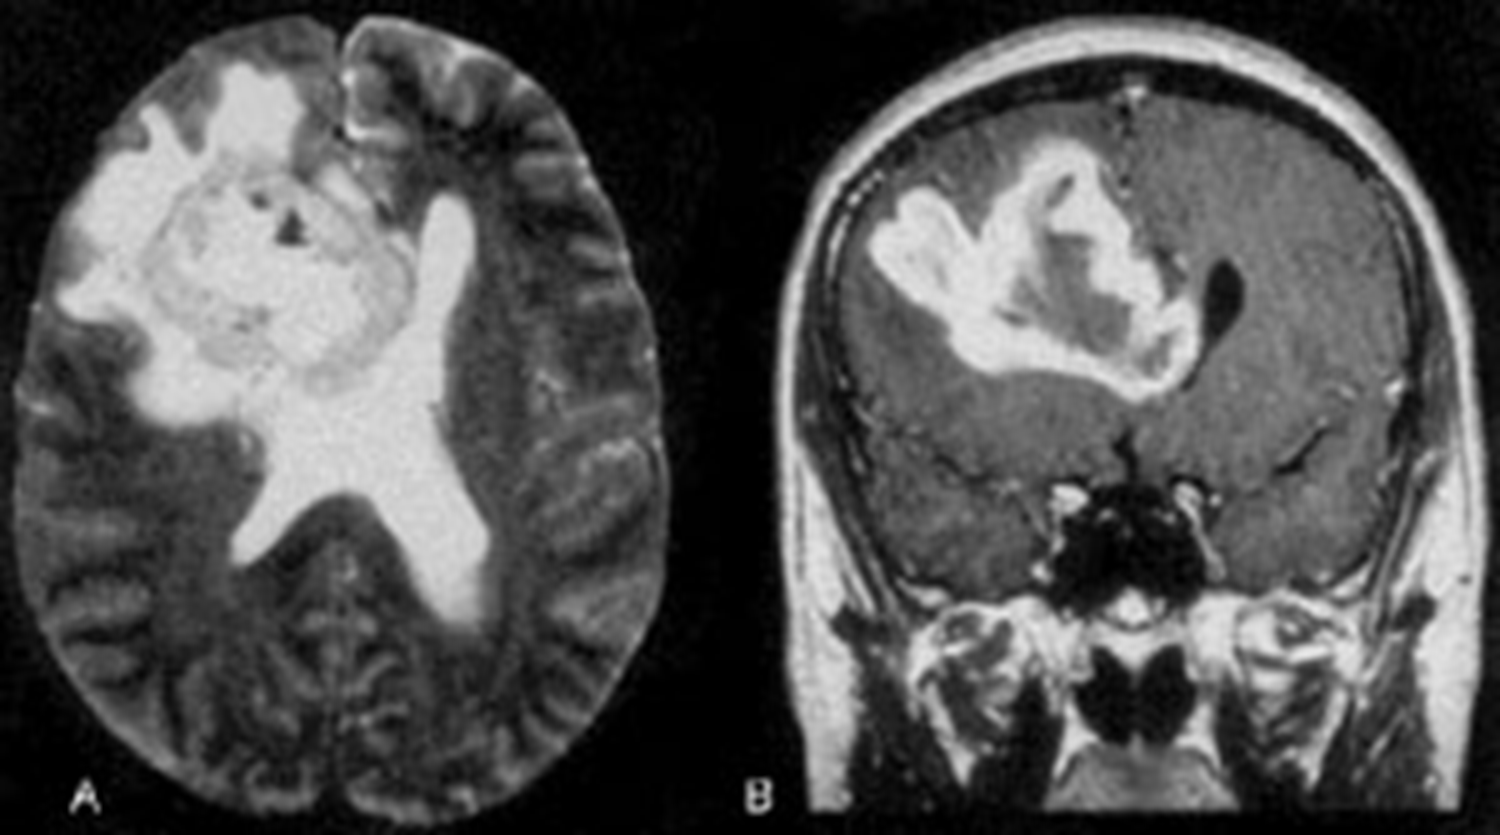

Peak incidence 50-60 years

Neoplasm occupies both hemispheres through the corpus callosum

Irregular ring enhancing

Average 1 year survival

GBM

astrocytoma who grade 4

ring enhancing T1

crosses corpus callosum

necrosis in the middle

(This pattern could be GBM, abccess with correct picture of infection ,or primary CNS lymphoma, but most likely GBM)

Butterfly lesion

astrocytoma grade 4